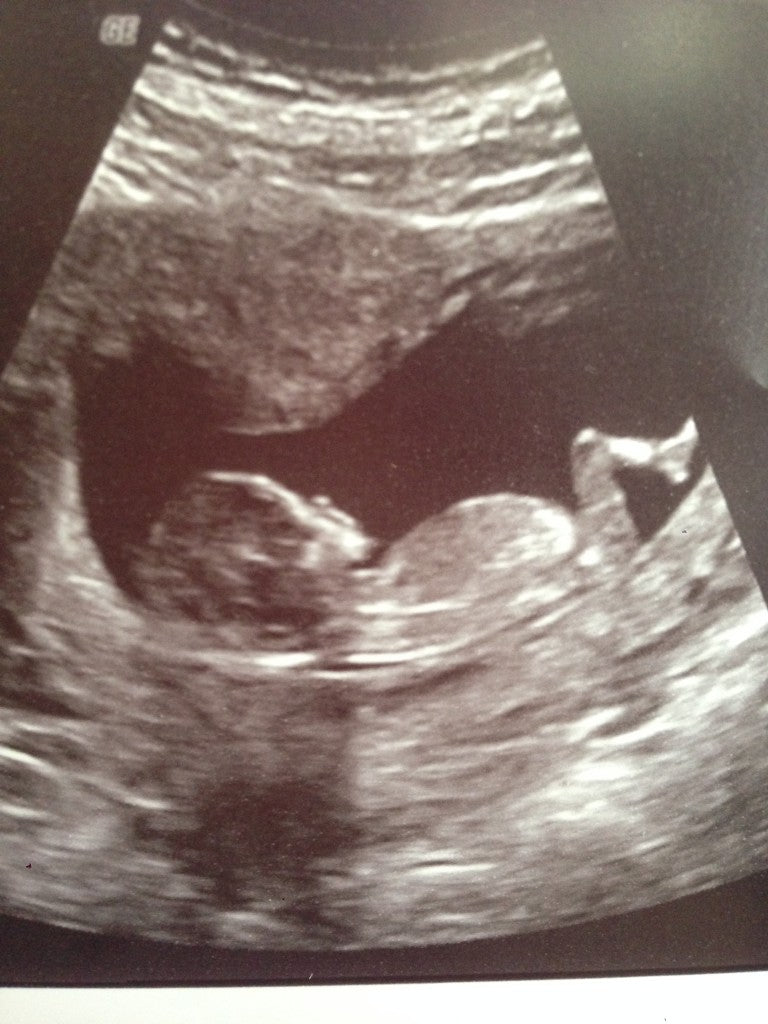

I got pregnant back in September 2013 and Peter and I could not be more thrilled. I think Peter had wanted to be a father since the minute we met. I went back and forth, physically craving children when I was 30, feelings of indifference from 32-33, but recently that began to change again and at the ripe old age of 34, we went for it.

And that is my message to any of you who are pregnant or thinking of becoming pregnant. Revel in the joy that is making a new life, but don’t take life itself so seriously that you don’t enjoy the journey. Of most people, I obviously understand the importance of a good diet. And I know what I will do to get back on track, but in the meantime, I’m not going to give myself grief over the poor choices I occasionally make. Things with baby Lois Marie and I are tracking along nicely according to our kind midwives and we cannot wait to welcome her into this world come June.